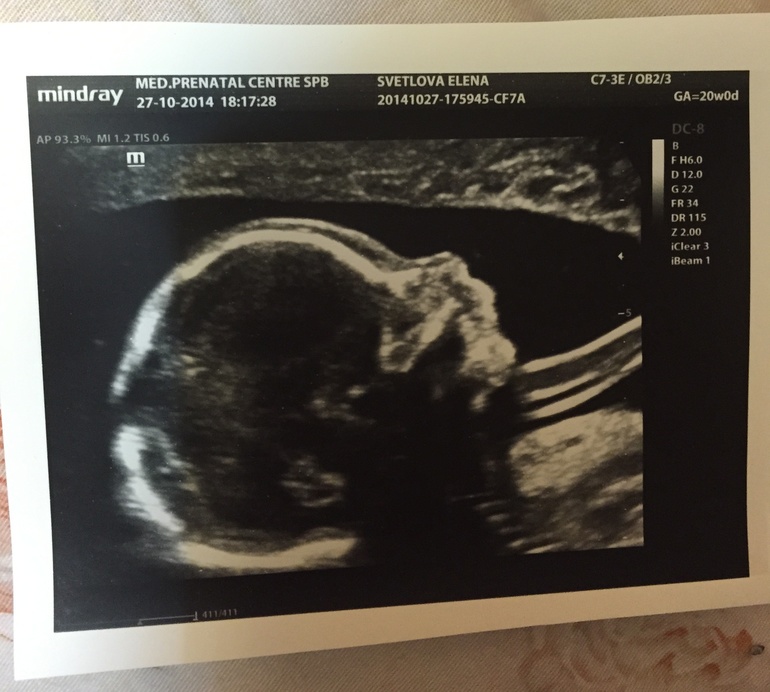

А это в 20 недель - 27.10.2014 г.